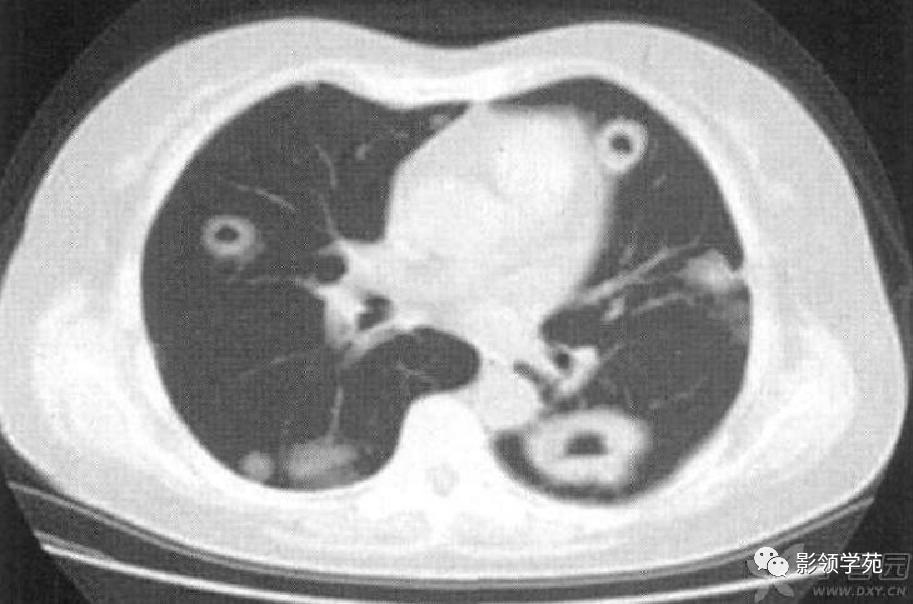

肺内多发结节和肿块是肺Wegener肉芽肿最常见的影像征象,表现为两肺散在分布、多发大小不等类圆形结节或肿块影,以两肺中下野分布多见。部分结节和肿块内可见空洞,洞壁多较厚,内缘光滑或不规则,空洞呈边缘性强化。合并感染时空洞内可形成液-气平面。结节或肿块周围一般都有较短毛刺,部分病灶有长毛刺与邻近的胸膜相连,表现为胸膜凹陷征。这与病理上结节周围存在大量成纤维细胞以及以纤维化形式愈合有关。

结节或肿块周围可见晕轮征、供养血管征。晕轮征提示肺结节或肿块出血,CT表现为结节或肿块周围磨玻璃密度影;供养血管征CT表现为血管影进入结节或肿块内,提示病变以血管为中心生长。

肺实变多由于肺泡出血所致,毛玻璃样密度影代表肺实变的早期阶段。楔形病灶是另一类较常见肺部CT 表现,肺梗死的病理基础是坏死性血管炎累及小动脉及小静脉引起的出血性肺梗死,CT表现为肺内楔形病灶,边缘清楚或不清楚,尖端指向肺门,宽基底位于胸膜面,可以看到血管进入征象及胸膜的增厚。

病例3:双肺多发结节伴空洞,部分空洞见气液平面。

病例4:左肺斑片状实变,右肺中下叶结节灶,中叶结节见供养血管征。